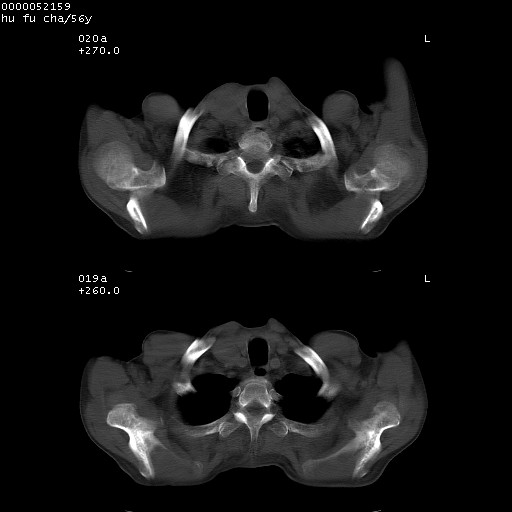

以下是引用zsl6918在2008-8-25 22:47:00的发言:[br]胸骨,胸椎及肋骨均可见多发转移表现,肝内低密度结节不除外转移。原发灶可能在右肺。双侧可见支扩表现。

以下是引用宇宙ct在2008-8-25 23:26:00的发言:[br][br] 胸骨,胸椎及肋骨均可见多发转移表现,肝内低密度结节不除外转移。原发灶可能在右肺。双侧可见支扩表现。 [br] [br]

以下是引用卜一在2008-8-26 8:02:00的发言:[br][br] 支持:肺癌并肺内,胸骨,胁骨,胸椎及肝内转移!另:左肺支气管扩张征伴感染! [br]

以下是引用zjzjr在2008-8-26 11:03:00的发言:[br]支持:肺癌并肺内,胸骨,胁骨,胸椎及肝内转移!另:左肺支气管扩张征伴感染!